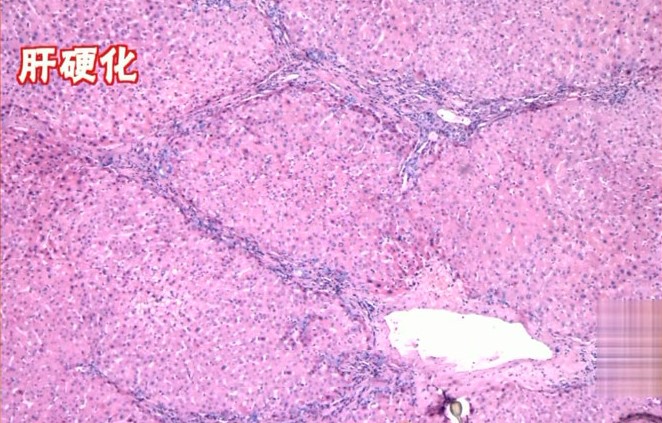

4)肝硬化

往下发展进入肝硬化期,这时候,肝功能损害很严重了,肝脏可能因肿胀而增大也可能会萎缩。